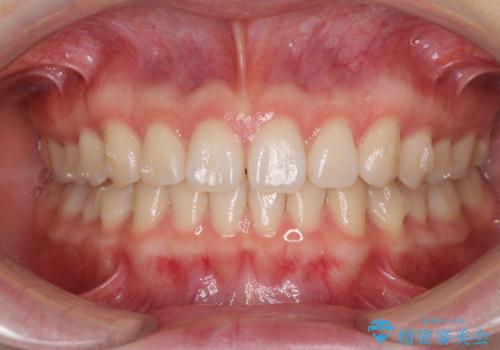

インビザラインによるすきっ歯の改善

- 上の前歯の隙間を気にして来院された患者様です。

インビザラインにより、隙間を閉じながら、隙間の原因であるディープバイトを改善していくこととしました。